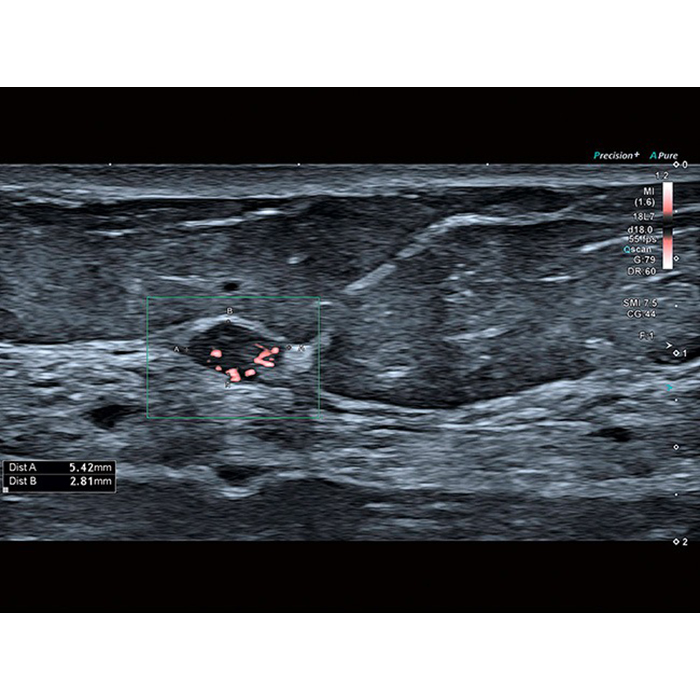

- SMI. Опция, упрощающая визуализацию микроциркуляторного русла. С ее помощью обследуются сосуды с низкой интенсивностью кровотока, изучаются наиболее тонкие структуры. SMI упрощает диагностику новообразований, минимизирует вероятность ошибки.

- Precision Imaging (прецизионная визуализация в результате получения и обработки данных от смежных сигналов))

- ApliPure+ (повышение контрастности изображений)

Технология получения и отображения информации о жесткости ткани, возможность проводить оценку динамики перфузии органов, тканей, образований, простой межреберный доступ благодаря специальным конвексным датчикам, возможность совмещать картинку в режиме реального времени с прежними данными МРТ, КТ, УЗИ, детальная визуализация плода в 1 триместре, технология трекинга миокарды и другое. Конкурентная цена и широкая продуктивность УЗ сканера Toshiba (Canon) a450 делают его покупку выгодным капиталовложением и выводят медицинское учреждение на более высокий уровень обслуживания пациентов.Область применения

Аппарат является универсальной моделью и подходит для разных областей диагностики. Его используют в кардиологии, педиатрии, сосудистой хирургии и т. д. Система совместима со многими преобразователями Aplio и позволяет врачам ставить точные диагнозы. Подходит для стационарных отделений и поликлиник, может использоваться в больших медицинских центрах.Система Canon Aplio A450 поддерживает исследования

- Маммология

- Исследование сосудов